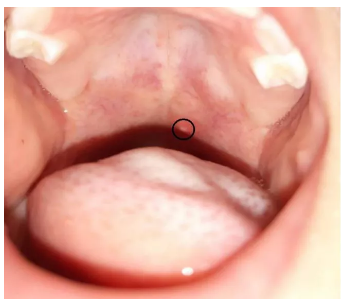

當孩子被皰疹性咽峽炎盯上,可能會出現急性的發熱、咽峽部的皰疹。

另外,由于口腔存在皰疹,孩子進食時會出現疼痛,因此會出現不愿意進食,同時流口水癥狀比較明顯,也可以伴隨有流鼻涕、咳嗽等呼吸道癥狀。

皰疹性咽峽炎需要與手足口病相區別,兩者都是由腸道病毒感染引起的,但皰疹性咽峽炎不會出現皮膚的皮疹。